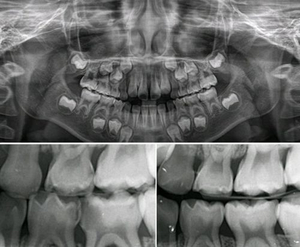

지난 글에서는 치과에도 10여 개의 전문적인 영역이 있다고 소개해 드렸습니다. 소아치과, 구강외과, 구강내과, 보존과(신경치료과), 치주과, 교정과, 보철과, 구강방사선과, 예방치과, 통합진료과를 설명해 드렸지요.이번부터 각 과에 이루어지는 진료에 관해서 설명해 드려 이해의 폭을 넓히고자 합니다.* 치아의 해부학적 구조, 치아의 또 다른 세상치아는 단단한 법랑질(enamel)로 덮인 외부층, 그 밑의 상아질(dentin), 그리고 중심부의 신경과 혈관이 모여 있는 치수(pulp)로 구성되어 있습니다. 이 치수는 치아의 ‘심장’이라